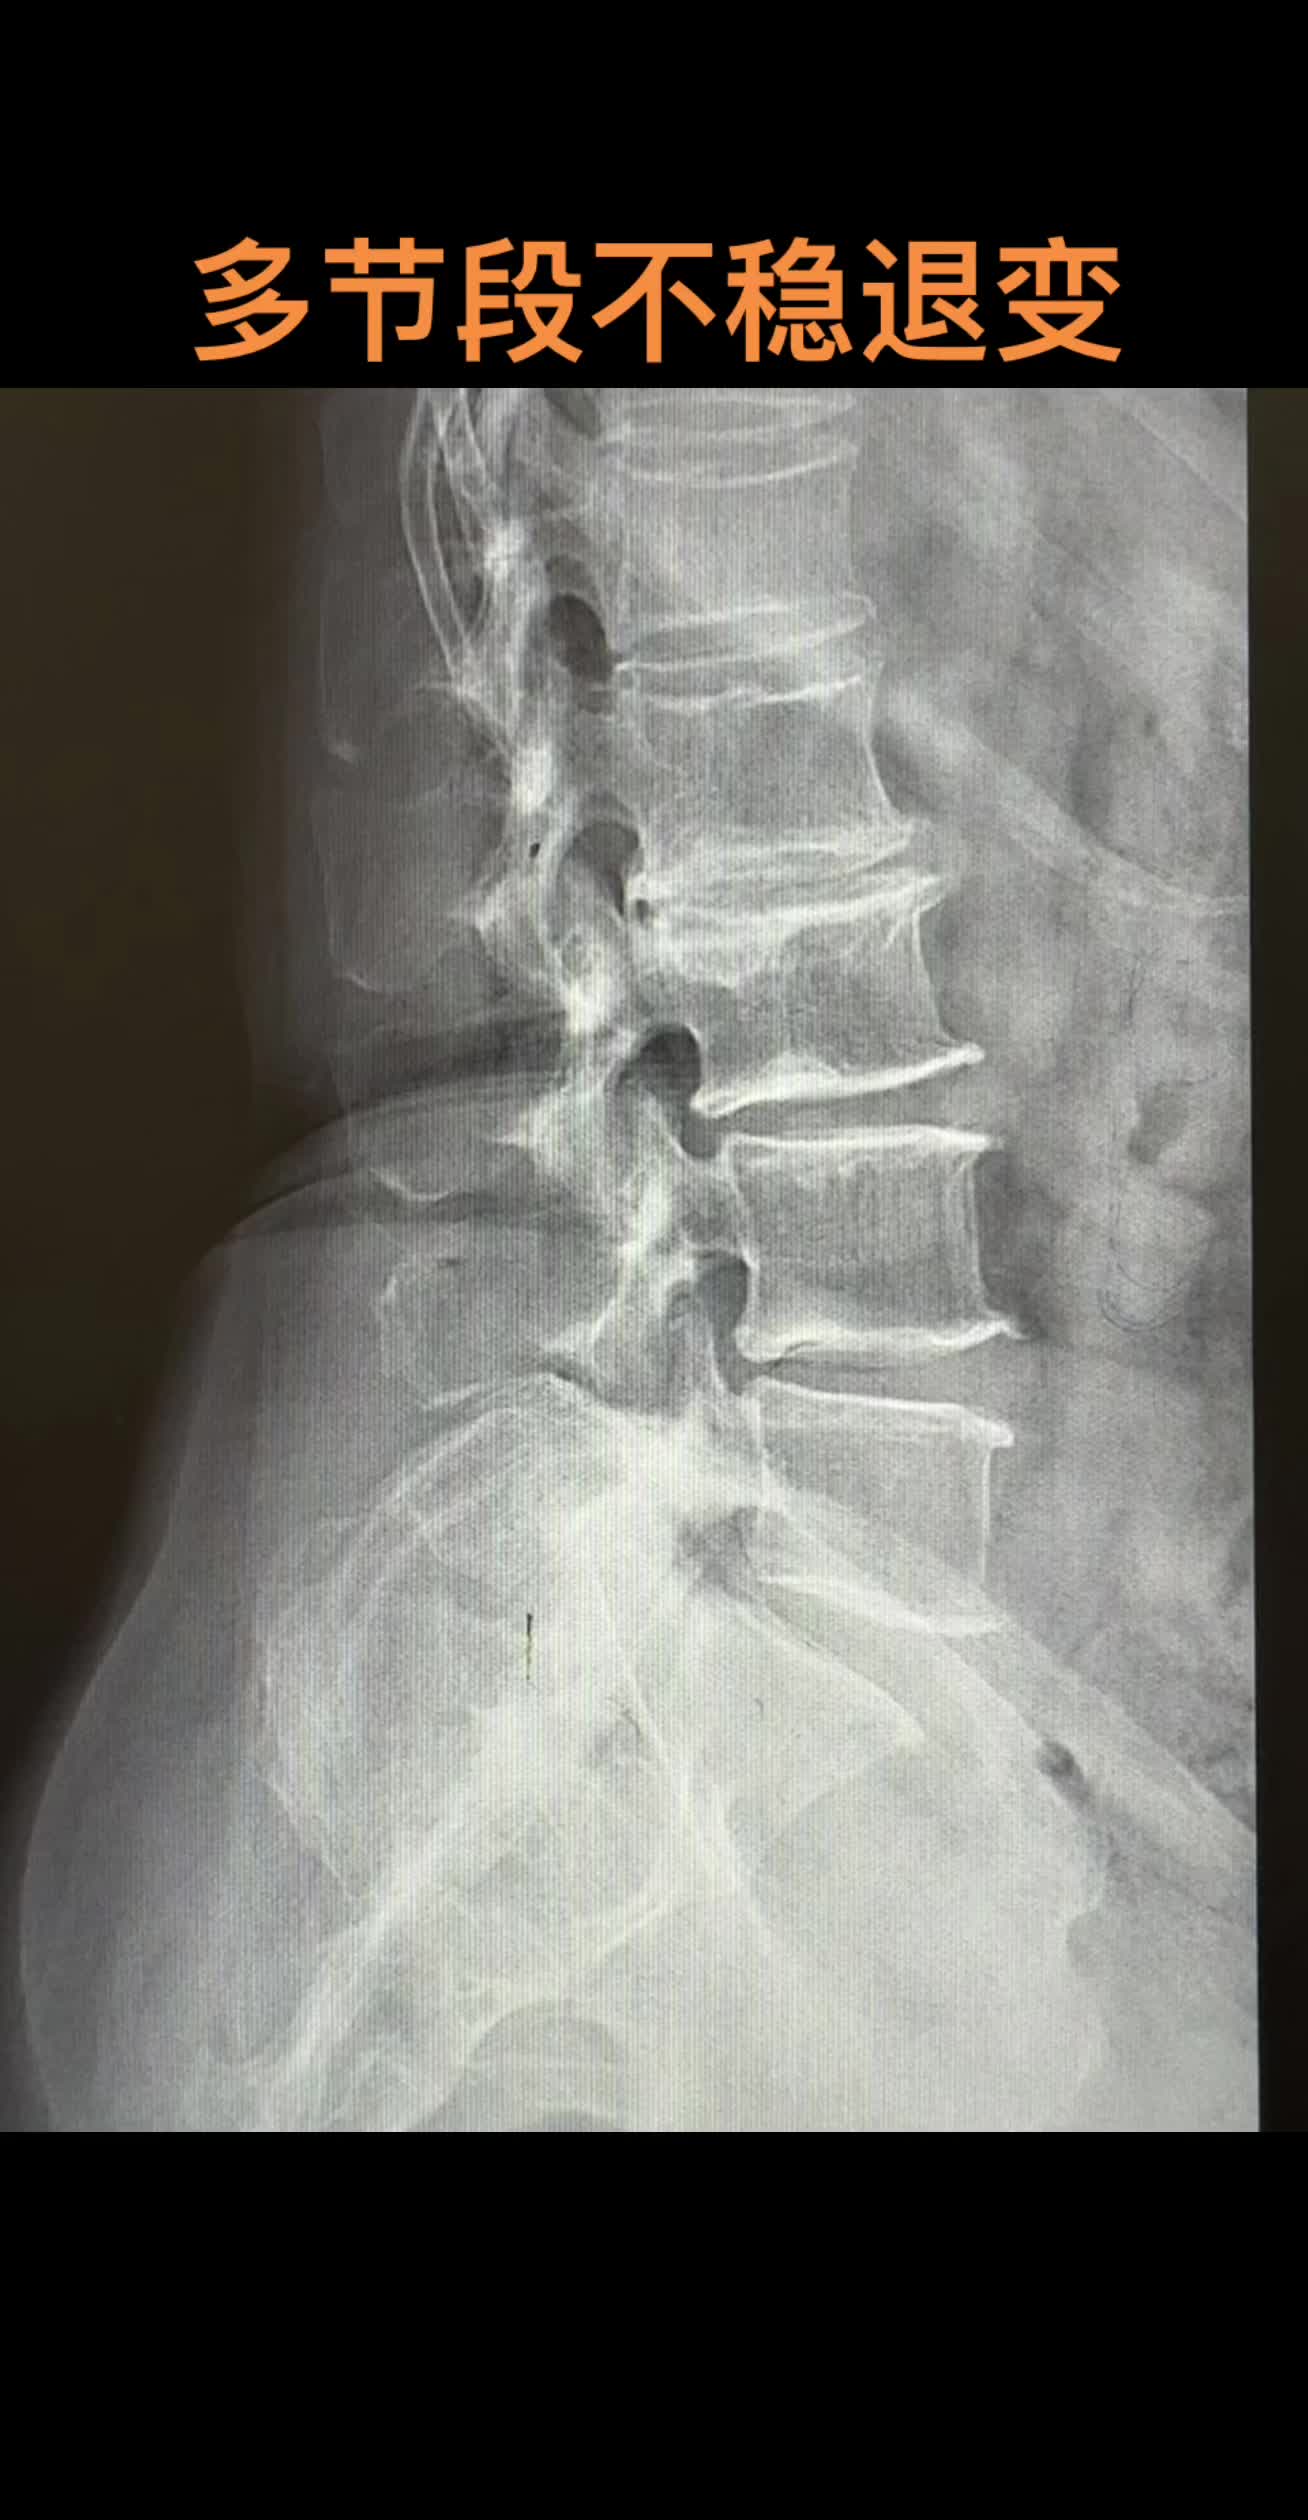

腰痛 骨质增生教科书般的退行性腰椎病

腰痛 腰椎退行性变骨质增生腰椎滑脱 教科书般的退行性腰椎病